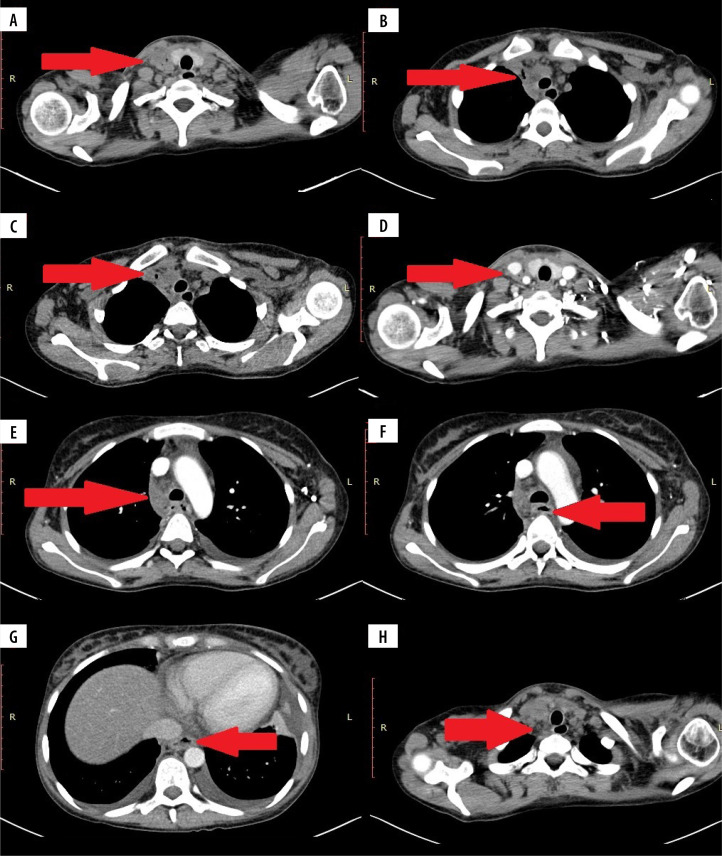

克罗恩病(CD)是临床上越来越常见的疾病。医学的进步延长了患者的生存时间,引入了新的治疗方法,以及疾病本身的性质意味着我们看到越来越多的新的,不寻常的这种疾病的并发症。我们回顾了三例罕见的乳糜泻并发症,重点讨论了影像学检查中可能出现的非典型并发症。乳糜泻及其治疗的并发症可发生在不同的器官和系统,并以非常非特异性的方式表现出来。如果不被注意,它们甚至可能危及生命;因此,在临床实践中,在评估CD患者时考虑其存在的可能性是很重要的。在评估这些人的影像学检查时,我们应考虑不典型体征和影像学特征的可能性,并考虑它们是否与潜在疾病有关。

Crohn's disease (CD) is an increasingly common disease in clinical practice. The progress of medicine, which has resulted in an extension of the survival time of patients, the introduction of new treatment methods, and the nature of the disease itself means that we are seeing more and more new, unusual complications of this disease. We have reviewed three cases of rare complications of CD, with a focus on possible atypical complications that may be seen on imaging studies. Complications of CD and its treatment can occur in various organs and systems, and manifest in very non-specific ways. If unnoticed, they can be even life-threatening; therefore, it is important in clinical practice to take into account the possibility of their presence when evaluating patients with CD. When assessing radiological examinations of these people, we should take into account the possibility of atypical signs and radiographic features, and consider whether they may be related to the underlying disease.